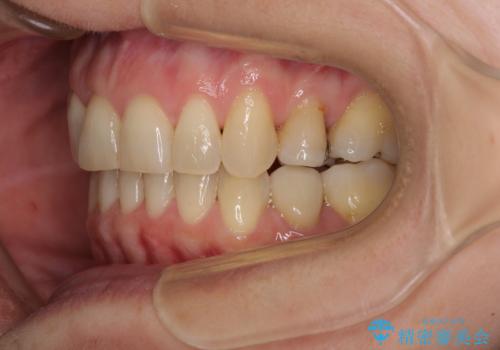

矯正の後戻りの改善と銀歯をセラミックに

- 上下前歯の叢生を気にして来院された患者様です。

費用を抑え、期間もあまりかけずに治療をしたいとのことで、インビザライン・ライトを用いて矯正治療を行うこととしました。

矯正治療後には、下顎臼歯の目立つ銀歯をセラミックインレーにて修復治療を行いました。

軽微な後戻りの治療であったため、十分に治療を行うことができました。

口を開けたときに金属が見えなくなり、患者様には大変満足していただきました。